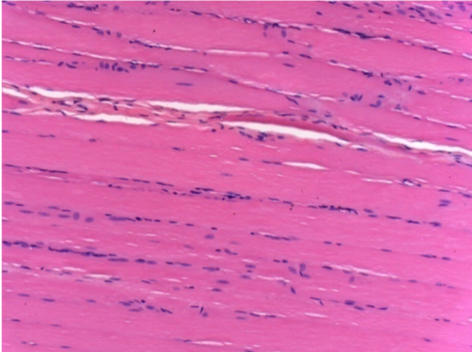

1 month after Endopeel Injection 0.1ml in the right pretibial muscle.

What is seen in black on the pictures is not a necrosis like could imagine some scientifics !

In fact, 4 conclusions have to be taken in consideration